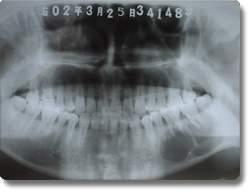

下颌骨肿瘤的手术治疗以往均采用口外颌下区皮肤切口,面部遗留疤痕。我科学习国外的先进方法,运用先进的手术器械,采用经口腔内切口入路方法,对下颌骨良性肿瘤,先行肿瘤切除,再同时采用钛合金成型再造板行下颌骨肿瘤切除后骨缺损缺损的一期修复。该方法的优点是下颌骨肿瘤的切除和骨组织修复再造均经口腔内切口一次手术完成,不再作面部皮肤切口,满足了患者的美容需要。该治疗方法与国际最先进水平保持同步。